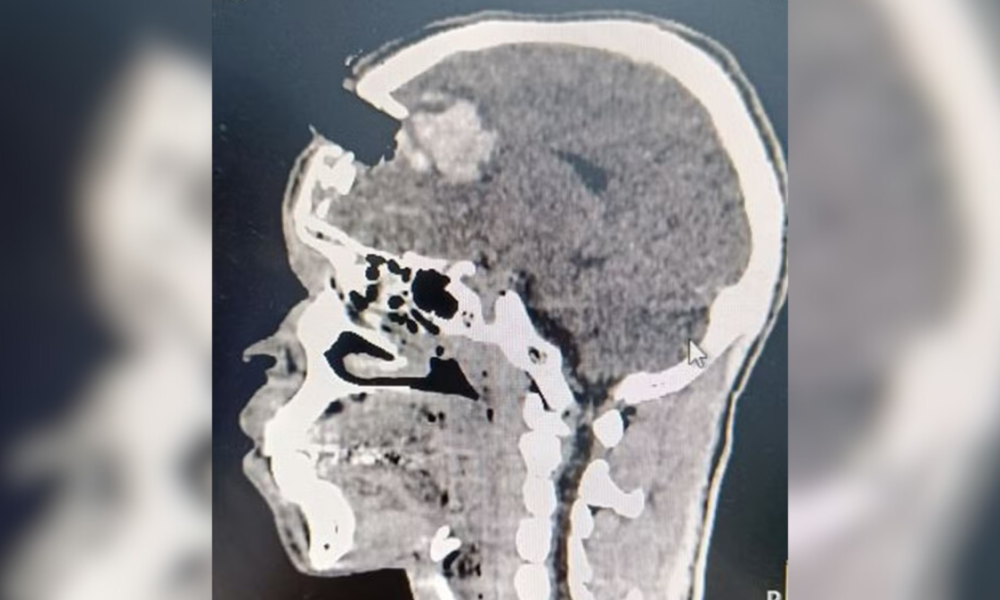

A direção do Hospital Adão Pereira Nunes informou que uma tomografia de crânio foi realizada e evidenciou uma fratura fronto facial, com fragmentos ósseos e contusão cerebral profunda.